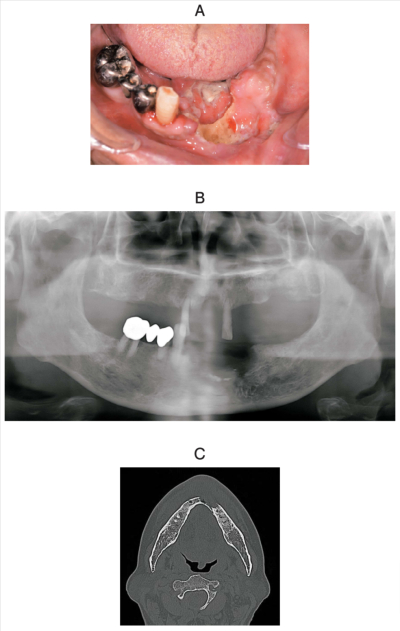

69 歳の男性。下顎前歯部歯肉の痛を主訴として来院した。半年前に自覚し、1か月前から増悪してきたという。初診時の口腔内写真、エックス線画像、CT及び生検時の H-E 染色病理組織像を別に示す。

診断名はどれか。1つ選べ。